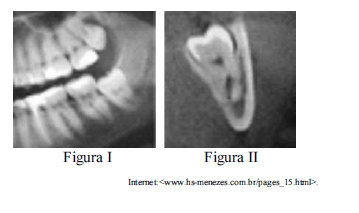

Situação hipotética: A radiografia panorâmica mostrada na figura I apresenta um terceiro molar inferior em posição vertical, com aspecto de curvatura nas raízes abaixo do canal mandibular do nervo alveolar inferior. O laudo da tomografia computadorizada, mostrado na figura II, aponta o siso 38 em infraversão e o canal mandibular posicionado entre as raízes mesial e distal desse mesmo dente, com o envolvimento de seu trajeto. Assertiva: Nesse caso, a remoção do siso deve ser feita mediante a separação das raízes para prevenir uma parestesia permanente do nervo alveolar inferior e metade do lábio inferior do mesmo lado do dente.